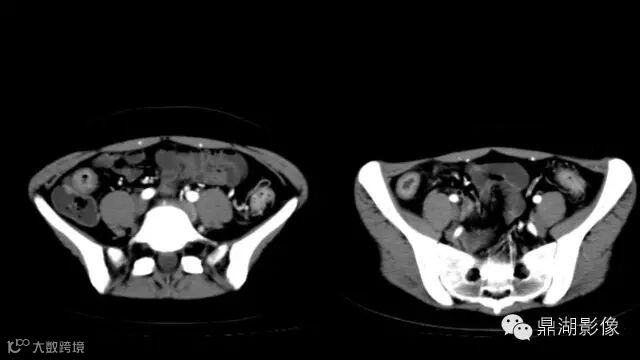

May it be ischemia?

There's a contrast uptake ,so I doubt it's ischemia

Well, ischemia need carefully observation.

do you know comb sign?

The comb sign refers to the hypervascular appearance of the mesentery in active Crohn disease.

It is the comb sign the most specific sign for crohn's disease.